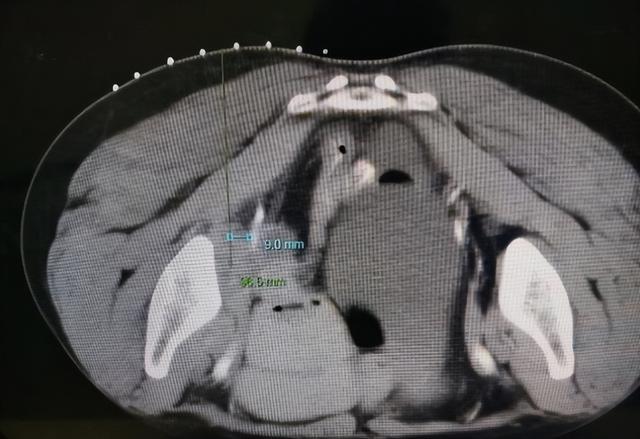

介入医学科副主任张军曙副主任医师反复研究雷女士的影像资料后,终于找到了一个不足9毫米的穿刺通路,然而,穿刺过程中既要避开邻近的髂内动脉分支,又要精准刺入肿块中心,这在临床上是一个难度相当大的操作。

黄水平主管技师和张军曙副主任医师默契配合,通过定位、做体表标记、打药、测量数据,顺利“点亮”通道,穿刺针精准穿入病灶中心,成功避开了不足9毫米的髂内血管分支,取样、送检一气呵成,张军曙副主任医师脸颊滑落的豆大汗珠和雷女士腹部的小小针眼宣告了这场高难度、高风险手术的圆满结束。